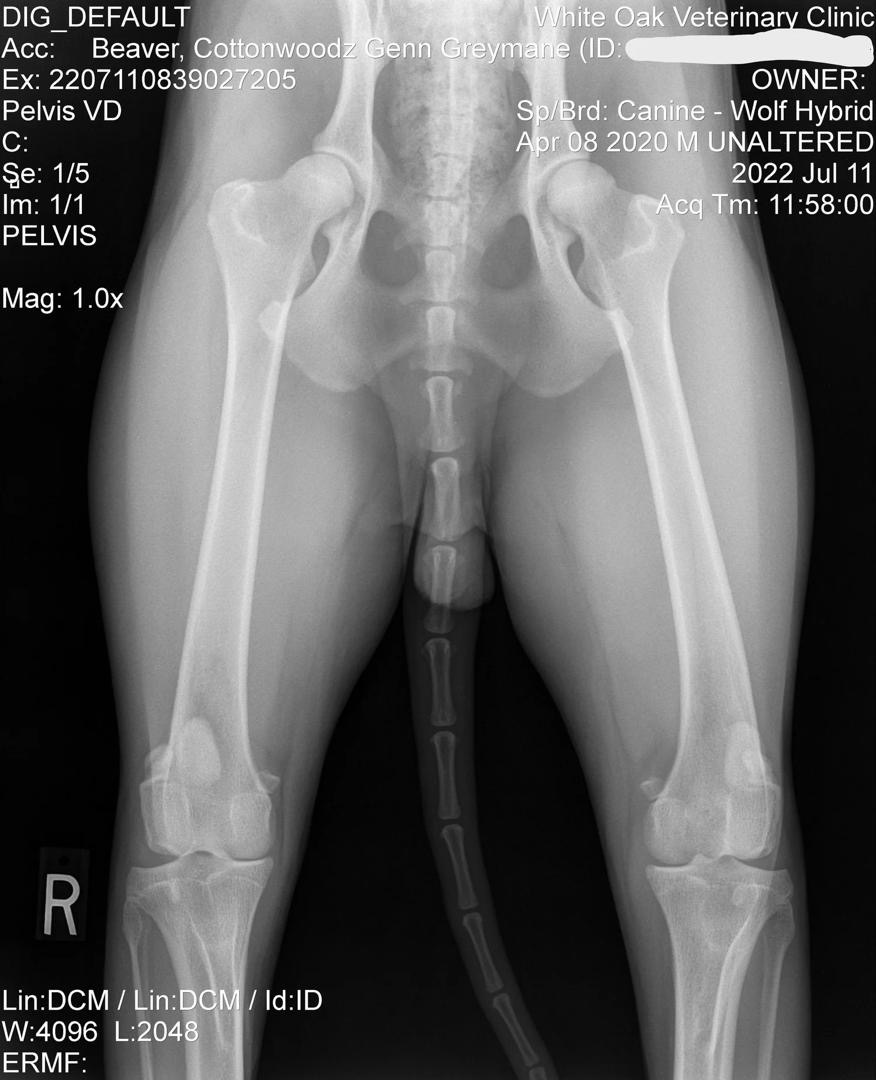

Official OFA Evaluations

Genn Official Hip X-Ray

Official Hip X-Ray

OFA Hip Evaluation: Good